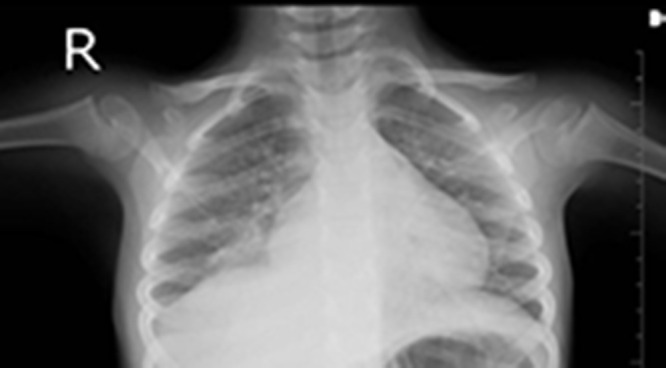

Methods: This case report presents the case of a 4 years and 5 months old patient diagnosed with invasive pneumococcal-associated pneumococcal infection in the context of SARS-COV2 infection.

Abstract Image